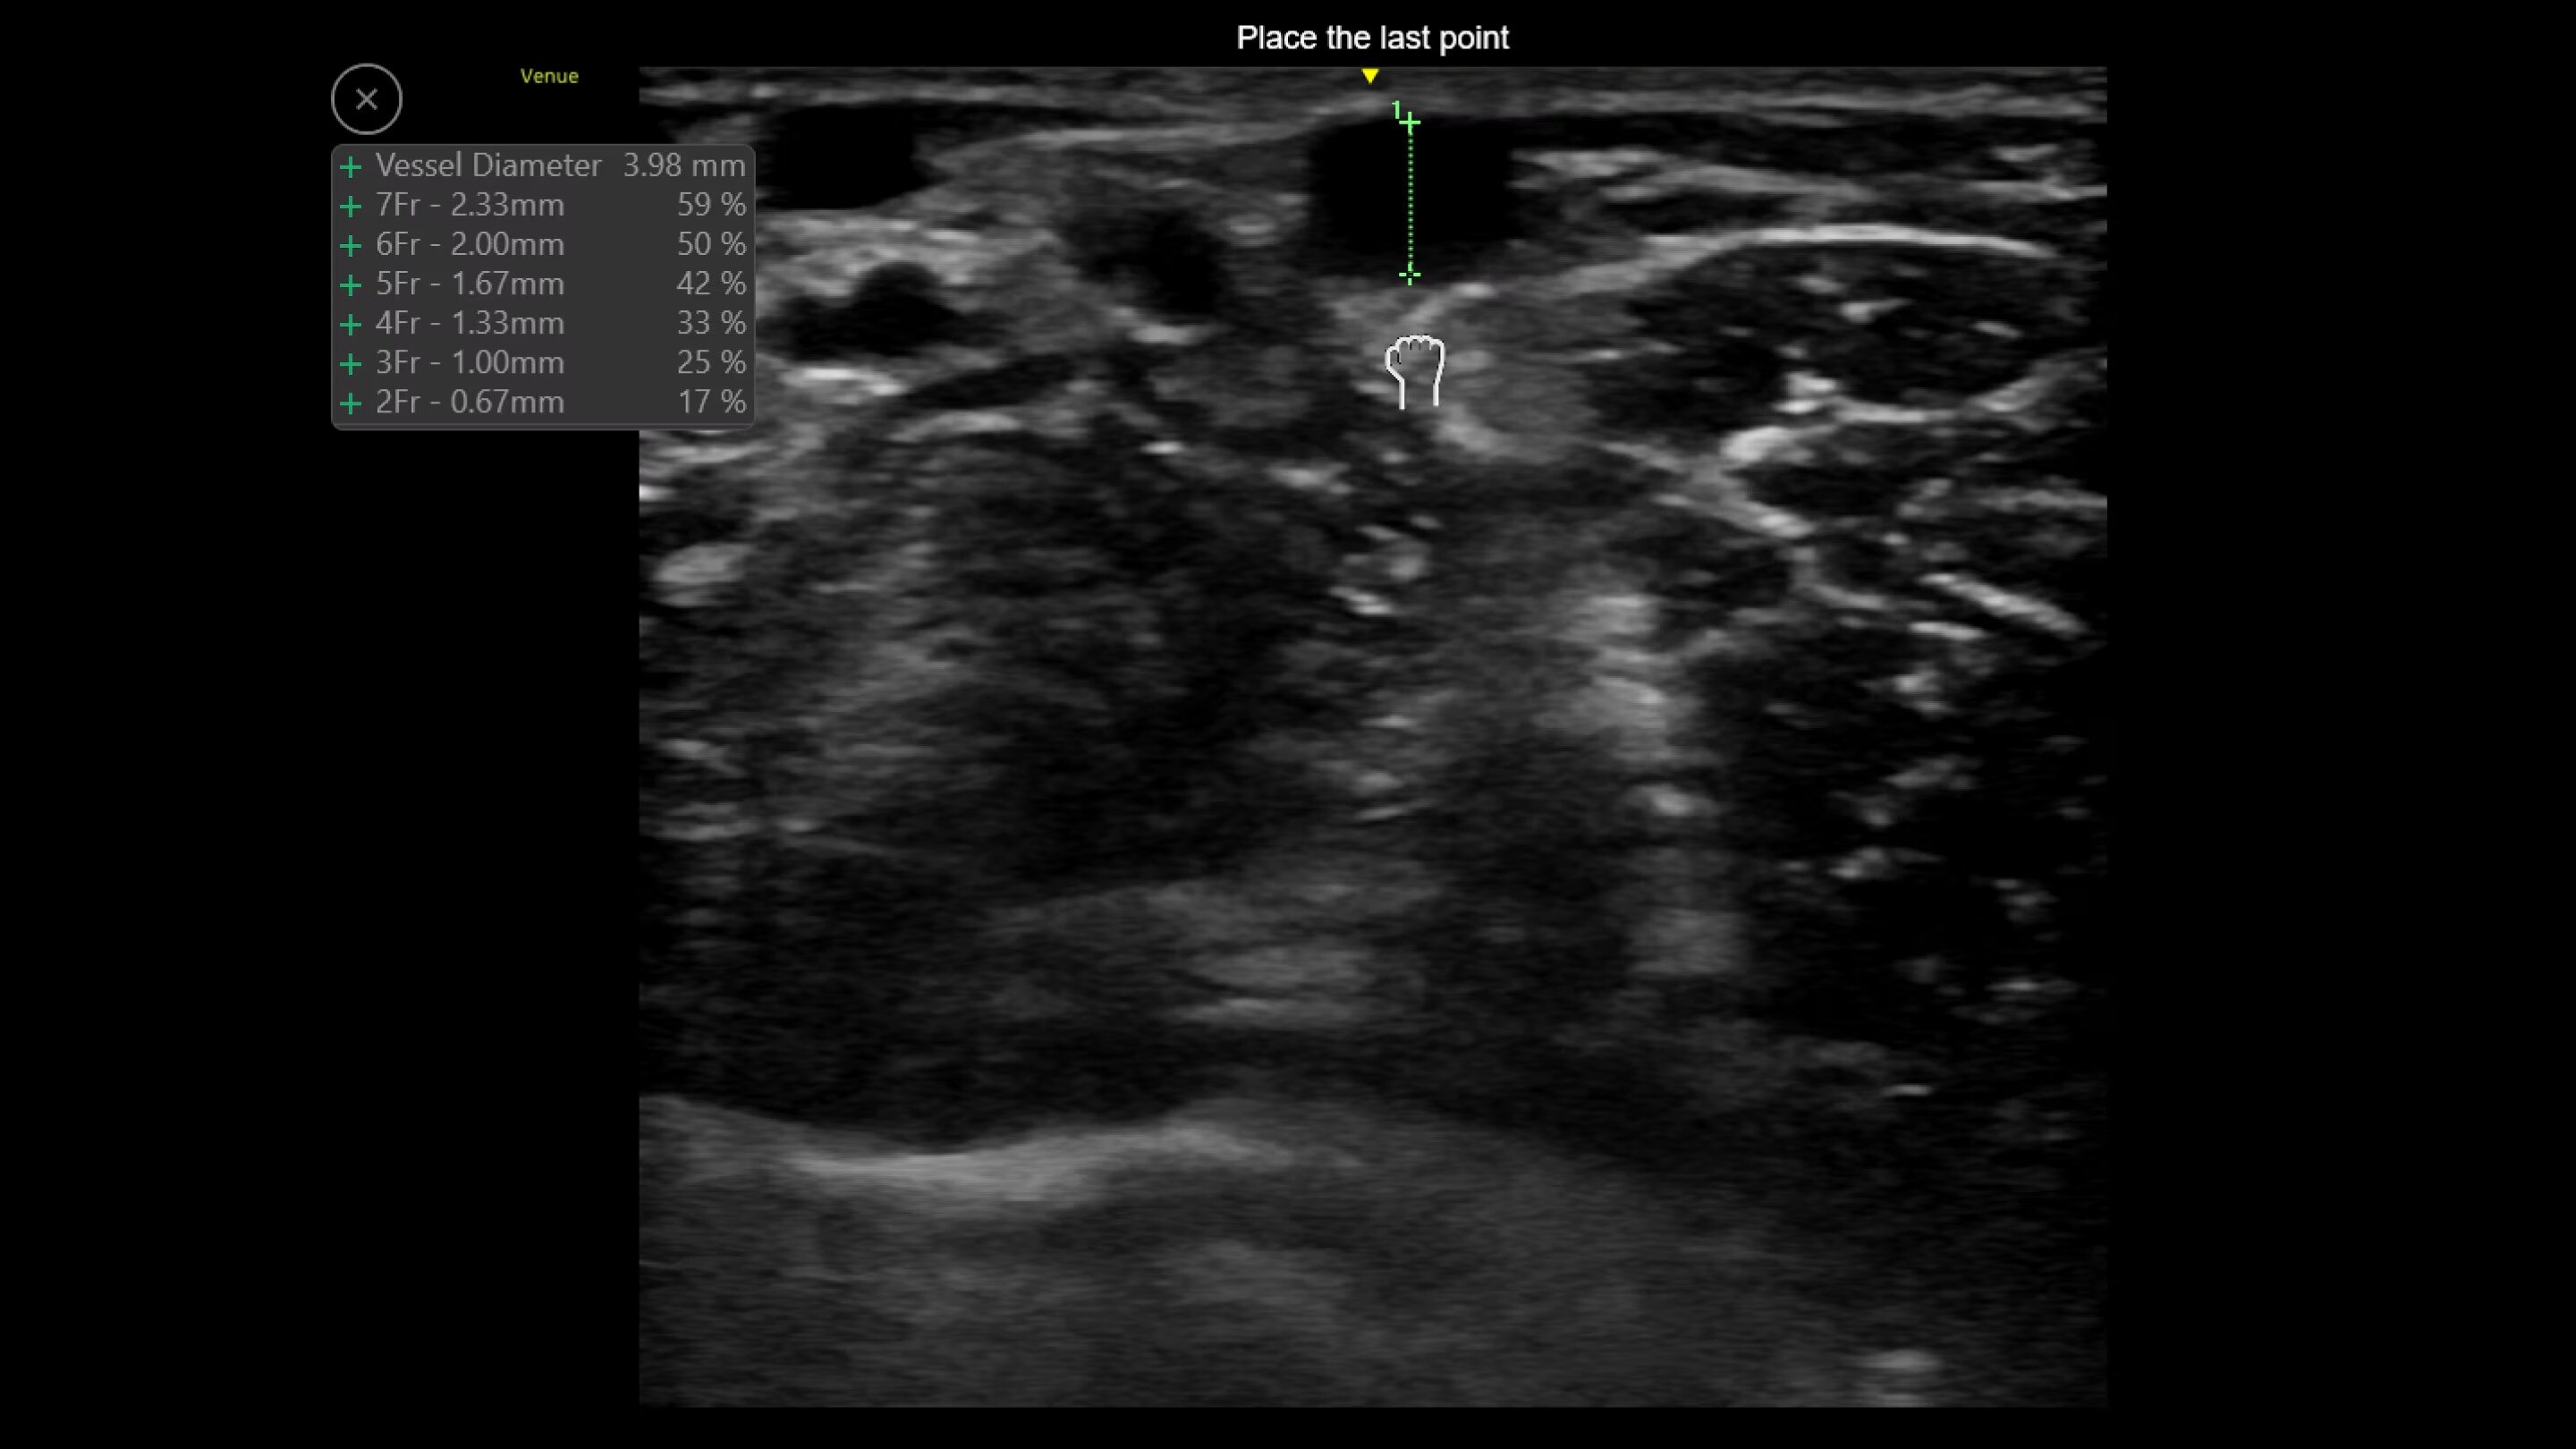

Catheter to Vessel Ratio

Accurate catheter selection tool

Selecting the wrong sized catheter can lead to catheter related thrombosis.2 Catheter to Vessel Ratio is a measurement tool that supports clinicians in selecting the appropriate sized catheter based on vessel diameter.